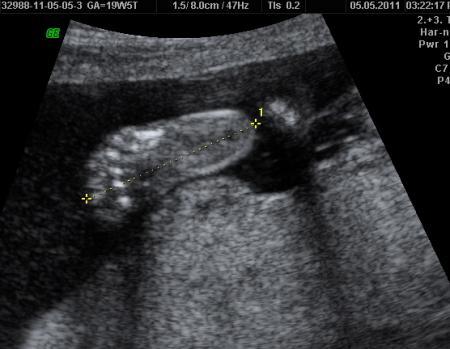

... meine heissgeliebten Fuesse

Bild zu

Hallo Agi, schön das dein >Tewrmin auch so gut verlaufen ist. Und die Bilder sind auch sehr schön. Toll das die da auch 3 D gemacht haben.Bei mir ja leider nicht. In die Füße von unserer kleinen habe ich mich auch verliebt.Haben sie auch genauso gesehen wie auf deinem Ultraschallbild. Bei uns waren die Füße auch schon 31,1mm. Zuckersüß was. Dann genieß erstmal die Freude über euren kleinen gesunden Mann Alles liebe